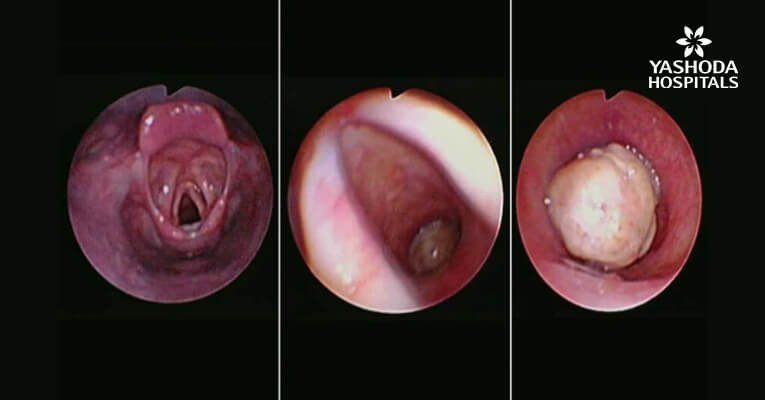

Contrast enhanced computed tomography (CECT) of neck and thorax reported intraluminal mildly enhancing polypoidal mass lesion measuring 2.58 x 1.54 x 1.51 cm (Cc X AP X Tr) in the upper trachea at the level of C6, C7 vertebral body. Significant luminal compromise was noted at the level of the mass lesion. Rest of the lung parenchyma was unremarkable. Flexible bronchoscopy examination revealed a large polyploidal growth approximately 3 cm from the vocal cords. The growth was moving with respiration and causing critical airway narrowing at the upper trachea (approximately 80%).

Diagnostic Flexible bronchoscopy Examination